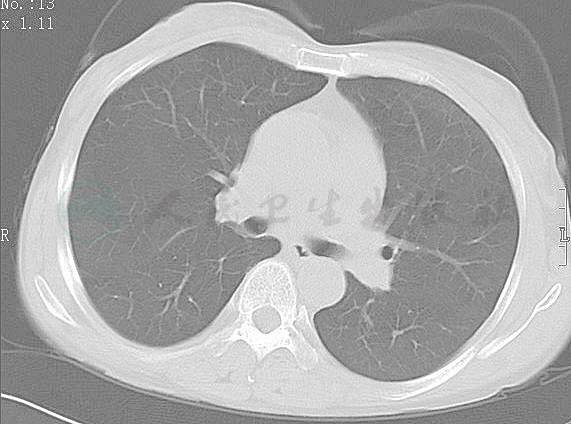

患者,女,50岁,因“咳嗽、咳痰、气喘伴间歇发热2个月”入院。患者于2008年4月初无明显诱因出现阵发性咳嗽,咳嗽剧烈时有气促、喘息,伴有咳白色泡沫痰,量中等,易咳出,并伴有不规则发热,具体体温不详,不伴咯血、胸痛和呼吸困难,不伴恶心、呕吐、腹痛、腹泻和尿频、尿急、尿痛等症状。在当地医院曾先后诊断为“慢性喘息型支气管炎”、“哮喘”、“鼻窦炎”,当地医院2008年5月22日查胸部CT提示双肺靠近胸膜处多处斑片状渗出性病灶(图1)。

图1-1 胸部CT提示双肺靠近胸膜处多处斑片状渗出性病灶(2008-05-22)

图1-2 胸部CT提示双肺靠近胸膜处多处斑片状渗出性病灶(2008-05-22)